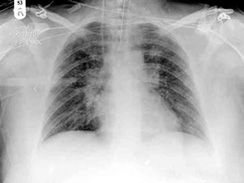

7.病程本症根據呼吸系統和中毒症狀分為輕症及重症,輕症一般在7~14天體溫下降,其他症狀也開始好轉,惟肺部陰影需2~6周才能完全吸收,重症病例於第5~6天以後,每有明顯嗜睡,面色蒼白髮灰,肝腫大顯著,喘憋明顯,肺有大片實變,部分患兒有心力衰竭,驚厥,半昏迷,肺部病變的恢復期更長,需1~4個月之久,3~4個月後仍不吸收者多有肺不張,日後可能發展成支氣管擴張,我們曾對3,7型腺病毒肺炎經過1~5年隨訪,30.1%有慢性肺炎,肺不張及個別支氣管擴張,以後又對3,7,11型腺病毒肺炎109例進行10年遠期隨訪,X線平片顯示45.3%有肺間質增厚,纖維化和慢性支氣管炎,慢性肺炎合併支氣管擴張占3.8%,支氣管擴張及慢性肺炎則各占4.7%,學齡前期與學齡期兒童的腺病毒肺炎,一般均為輕症,常有持續高熱,但呼吸道症狀及神經系統症狀不重,麻疹並發或繼發腺病毒肺炎時,則所有症狀均較嚴重,病情常易突然惡化,我們曾觀察34例(1964~1980)11型腺病毒肺炎的臨床表現,發現與3,7型腺病毒肺炎的症狀無明顯差異,但重症及死亡者與3型相似,而較7型者明顯為少,我們曾觀察38例1~5個月小嬰兒腺病毒肺炎(3型20例,7型12例,11型6例,1981~1983),8例為毛細支氣管炎,30例為肺炎,臨床特點為:多低度或中度發熱,熱程短,無肺部實變體徵,胸片以小片陰影為主,萎靡,嗜睡等神經症狀的發生較6個月以上嬰幼兒少且輕,臨床上無法與呼吸道合胞病毒或副流感病毒肺炎區別,致使本組病例在病原學報告前無一例臨床診斷為腺病毒肺炎者。